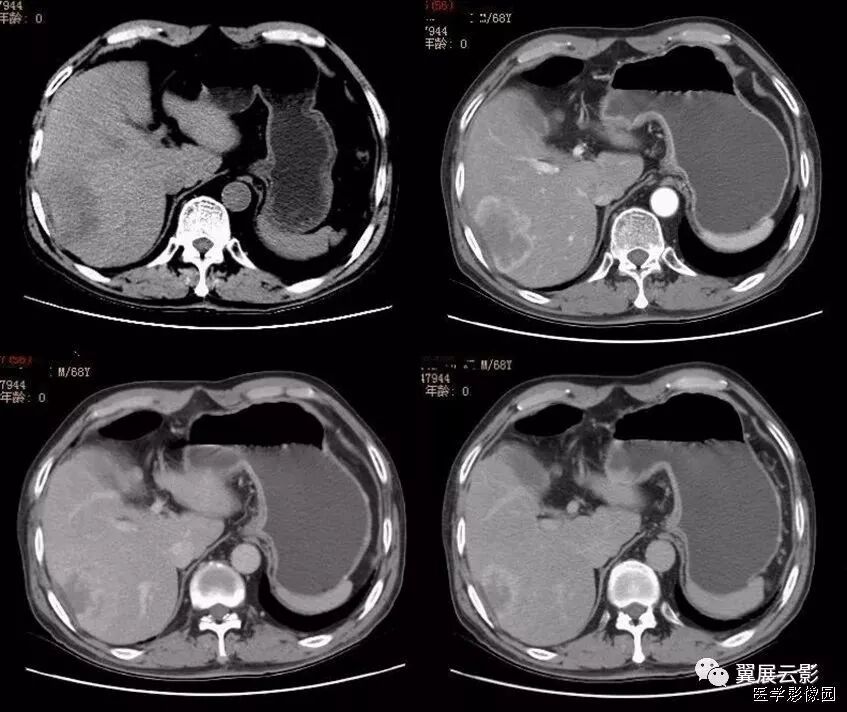

25、肝包膜凹陷征(肝包膜退缩征)

腹部CT扫描时,位于肝脏表面的恶性肿瘤,肝包膜内陷,失去原有的弧度,并与其相续的肝包膜构成一个完整的大弧度,谓之肝包膜凹陷征。

肝恶性肿瘤的发展过程中,小血管,小胆管阻塞引起局限性肝萎缩,肿瘤中央坏死、瘤周纤维组织增生并侵犯肝包膜等多种因素,致使肝包膜向肝内方向收缩,共同导致包膜凹陷征。

虽然肝包膜凹陷征在肝脏恶性肿瘤中出现率并不高,但邻近肝脏肿块的肝包膜凹陷征在许多种恶性肿瘤中都可以出现,包括肝细胞性肝癌、纤维板层性肝、肝内胆管细胞癌、肝转移瘸(原发肿增多为结肠癌、乳腺癌、类癌、肺癌、胆囊癌、胃癌、胰腺癌等)。其病理基础是瘤体中心由于代谢旺盛,血供相对不足,易发生坏死囊变,邻近肝表面的病灶坏死后埸陷,牵拉被膜进而形成脐样凹征。国外学者有认为肝包膜凹陷的机制是由于肿瘤内存在着纤维细胞,尤其肿瘤坏死区纤维细胞增生活跃,当肿瘤细胞侵犯肝包膜后,纤维细胞小均匀的收缩和牵拉,从而可产生肝包膜向内侧方的凹陷。

根据影像学特点将肝包膜凹陷征分成两型:

Ⅰ型,肝包膜凹陷征范围较小,呈反弓状或脐凹状,表面光滑,肝包膜无增厚,凹陷区少有腹腔积液;

Ⅱ型,肝包膜凹陷征范围较广,呈凹坑底状,表面欠光整,肝包膜常不规则增厚,凹陷区多伴腹腔积液。

据文献报道,除巨大肝脏血管瘤偶尔出现肝包膜凹陷征外,良性肿瘤一般不会出现此征,这是由于良性肿瘤一般不存在这种病理改变,所以此征象对肝脏恶性肿瘤的诊断具有特异性,但对鉴别恶性肿瘤的细胞来源并无特异性。此外,肝包膜附近的肝脏炎性病变,尤其是肝脓肿也可出现肝包膜表面凹陷征;同时要注意与肝硬化进行鉴别诊断,典型肝硬化肝表面凹凸不平,呈波浪状或驼峰状,肝包膜凹陷多发且较表浅,CT平扫再生结节可呈多发等密度或高密度影,但增强扫描门脉期和延迟期结节影呈等密度,使凹陷区与邻近肝实质密度基本一致。

以下两例均是胆管癌,可以看出有明显的肝包膜内陷: